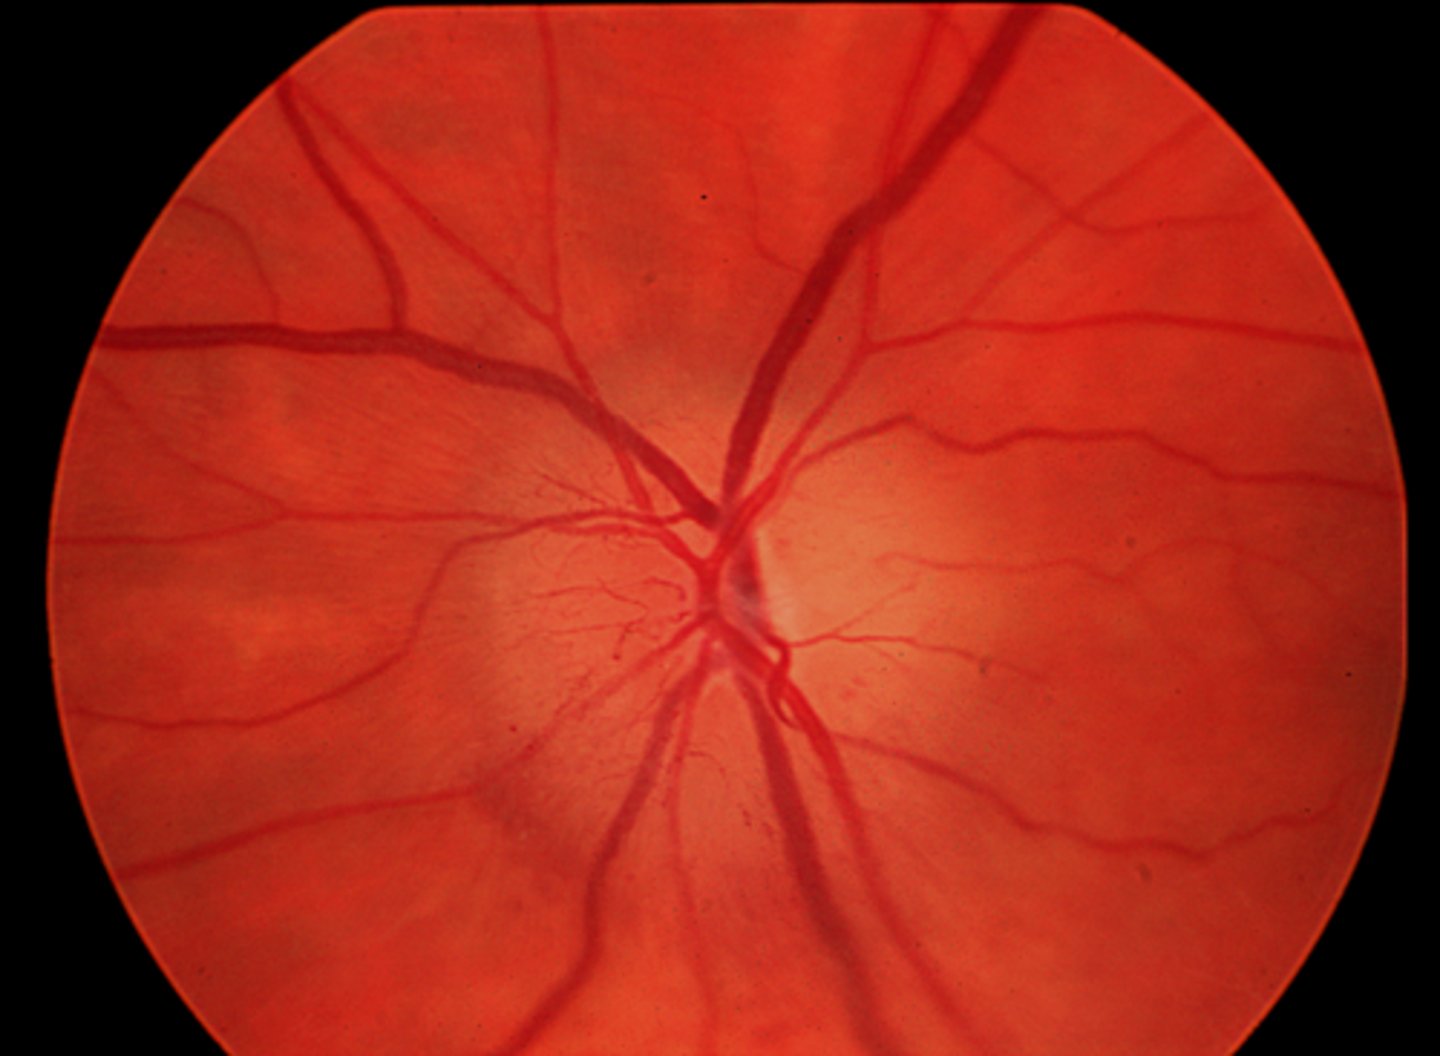

What cause of descending optic atrophy is seen here?

neoplasm in cranium (craniopharyngioma) causing compression